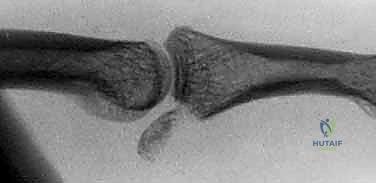

* FIG 4 • Unstable PIP palmar lip fracture-dislocation. Extensive damage has occurred to the palmar lip of the middle phalanx, but the dorsal cortical margin and a small amount of dorsal articular cartilage remain intact. Even slight dorsal subluxation can be detected by looking for a V-shaped gap between the middle and proximal phalanges.

*

* FIG 4 • Unstable PIP palmar lip fracture-dislocation (continued). Note the "V" sign indicating persistent dorsal subluxation.